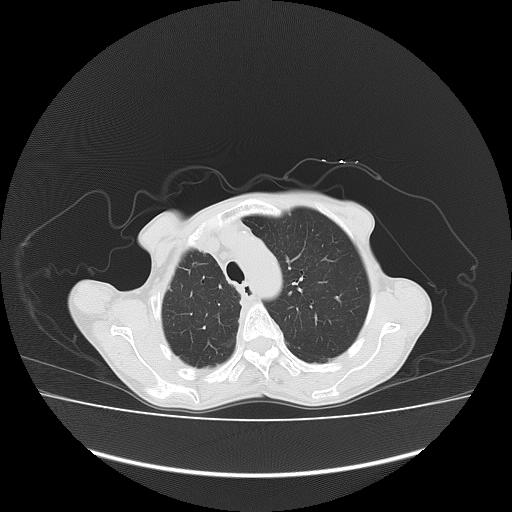

标题: CT16930:女 59 胸痛6个月 胸水脱落细胞学见瘤细胞 [打印本页]

标题: CT16930:女 59 胸痛6个月 胸水脱落细胞学见瘤细胞

可见多发肺内病灶,且胸膜病灶较多有圆球状而非丘状,多考虑胸膜转移瘤伴胸腔积液,右侧胸廓缩小固定,且部分病灶呈丘状,尚不除外恶性胸膜间皮瘤伴肺内转移

右侧胸膜增厚,局部呈结节状增厚,右侧胸腔少量积液。双肺未见确切肿块影。纵隔未见淋巴结肿大。气管、支气管通畅。考虑右侧胸膜间皮瘤(恶性?)可能性大。不除外癌性胸膜炎。

恶性胸膜间皮瘤伴肺内转移可能性大;或胸膜、肺内均为转移瘤,左肺下叶亦见多发小结节影。

右侧广泛胸膜增厚,局部呈结节状增厚,右侧胸腔少量积液。双肺未见确切肿块影。纵隔未见淋巴结肿大。气管、支气管通畅。考虑右侧胸膜间皮瘤(恶性?)可能性大。支持!